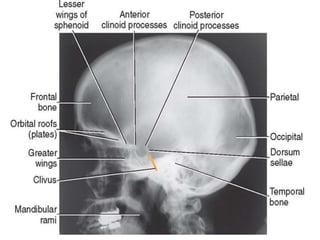

CRANIUM.

Anatomy.

• Is composed of the frontal, occipital, sphenoid and

ethmoid bones and the paired temporal and parietal

bones.